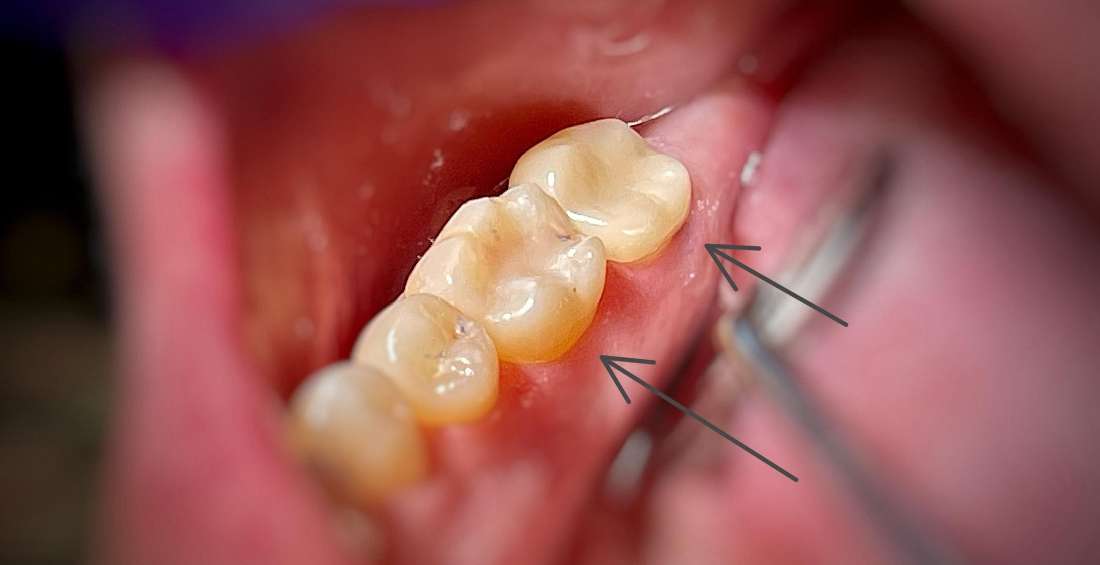

This patient came to our dental office in South Charlotte. One tooth lost most of its chewing surface and was cracked. We were able to save the tooth with a CEREC same day crown. Another tooth nearby had an old filling that was starting to break down. We restored this tooth with a composite white filling.